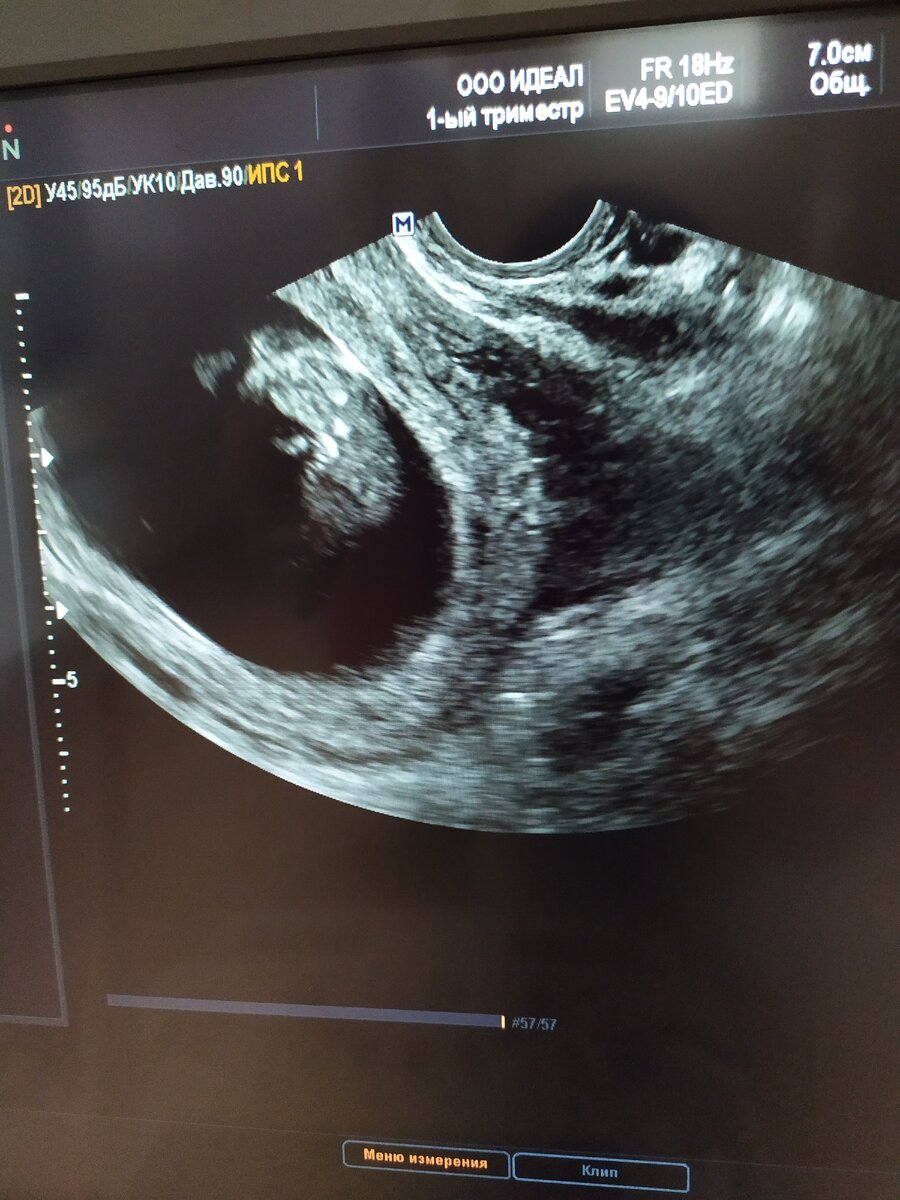

УЗИ платно делала (у нас, правда, только до 20 недель делают).